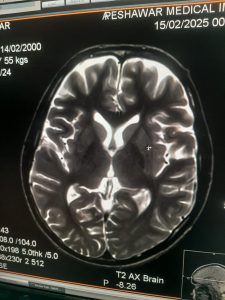

Successful Installation and Commissioning of Hitachi Echelon 1.5T MRI at Peshawar Medical Imaging (PMI)

This milestone marks our ongoing commitment to delivering reliable and high-performance MRI solutions throughout Pakistan. Congratulations to our dedicated engineering team for their excellence and professionalism. We are proud to contribute to advancing diagnostic imaging capabilities in the region.